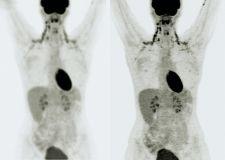

The side-by-side images demonstrate a typical positron emission tomography and computed tomography (PET/CT) combination image before (left side) and after applying Siemens Medical Solutions HD PET algorithm. The clarity achieved by HD PET is the result of a proprietary technology that optimizes the elements of image uniformity, resolution and contrast.

True V extended field-of-view (FOV) technology in HD PET reportedly improves 2 mm resolution to clearly visualize the smallest of lesions from the center to the edges. It provides twice the signal-to-noise improvement and near uniform spatial resolution throughout the FOV. HD PET incorporates millions of point spread functions (PSFs) in the reconstruction algorithms. Using measured PSFs, HD PET effectively positions the line of response in their actual geometric location, which dramatically reduces blurring and distortion in the final image.